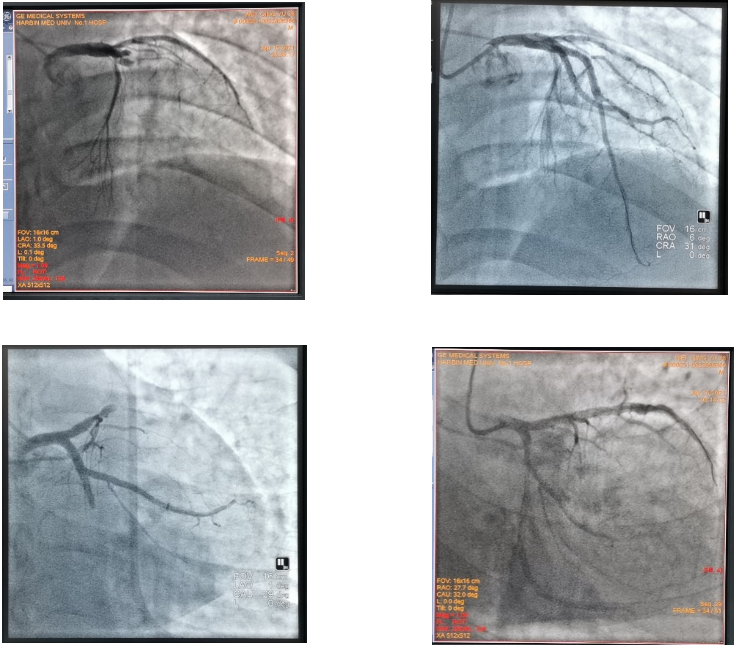

病例二:38岁年轻男患,术前造影示左前降支、回旋支急性双血管闭塞(左图)。于左前降支、回旋支血管顺利置入2枚支架,造影示左前降支、回旋支完全恢复血供(右图)。